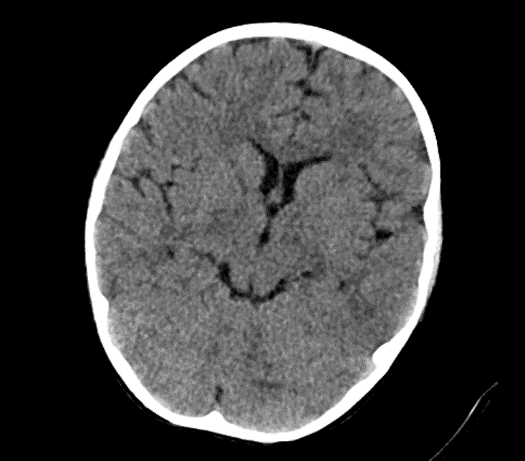

Due to the exacerbation of symptoms and onset of convulsions, a brain CT was conducted, which revealed no significant abnormalities.

Picture1.